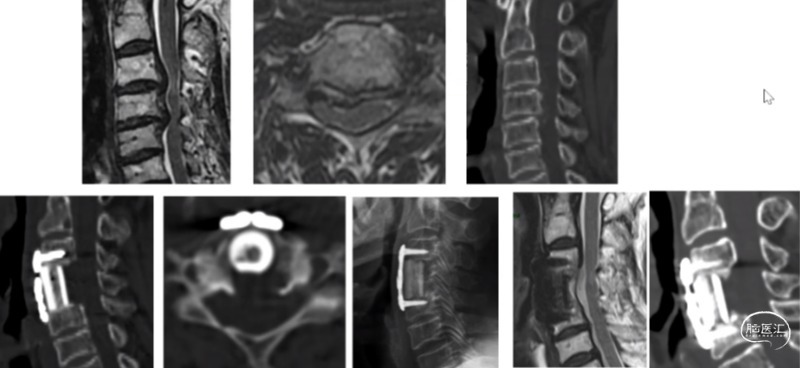

后纵韧带骨化:椎体次全切ACCF

整体迁移融合技术ACAF